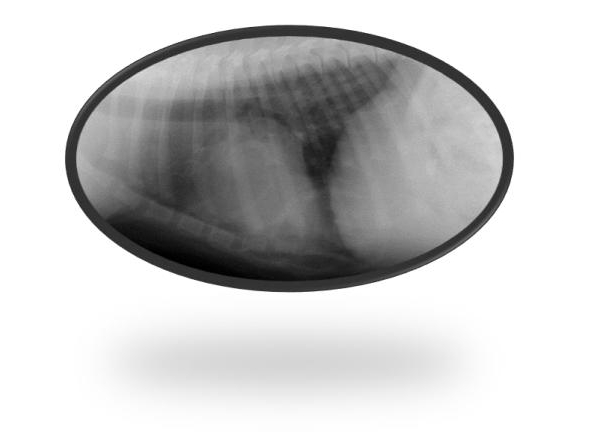

心膜横隔膜心嚢膜ヘルニア治療例

心膜横隔膜心嚢膜ヘルニア手術について、CT画像にて診断し腹部・胸骨正中切開術を行いました。